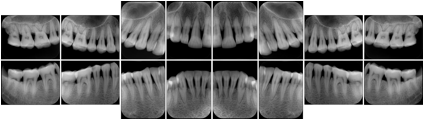

6 Standard + 4 Bitewing C Dental Image Layout

DL-P002E

Reference:

01

Standard

11, 12, 21, 22

11

32, 31, 41, 42

20

Bitewing

18, 17, 16, 15, 48, 47, 46, 45

21

17, 16, 15, 14 47, 46, 45, 44

23

27, 26, 25, 24, 37, 36, 35, 34

24

28, 27, 26, 25, 38, 37, 36, 35